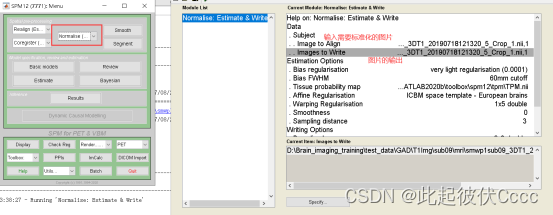

2.6 对图像进行标准化

使用spm进行标准化,这里选择上一步以及平滑后的图片